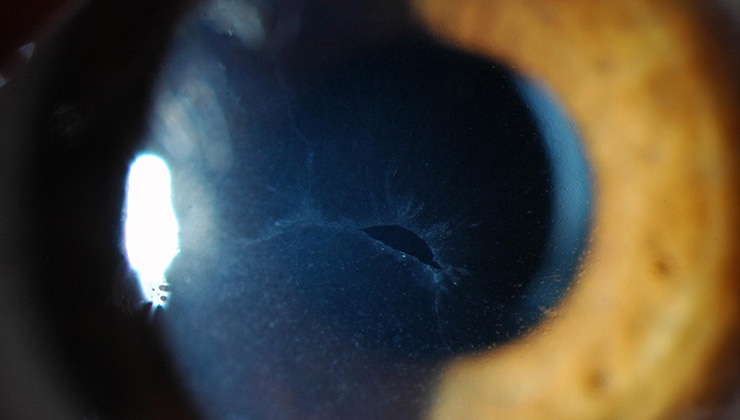

A corneal ulcer is an injury to the cornea that may become very serious if it is not treated in time.

Corneal ulcers cause the following symptoms:

• Pain (sometimes very intense)

• Photophobia

• Tearing

• Red eye

• Visual problems

• In very serious cases, some patients find it difficult to open their eyes

Treatment depends on the cause of the ulcer. If it is infectious, an intensive course of antibiotics and pain relief measures are prescribed.

It is essential that treatment starts as soon as possible, since corneal ulcers can cause permanent damage to the cornea if left untreated.